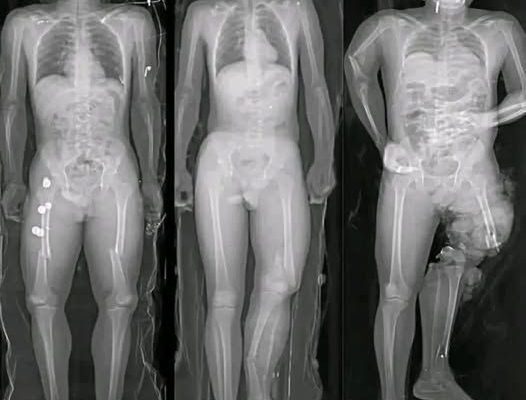

One of the most common claims in viral posts is that COVID vaccines “damage the heart.” This statement oversimplifies and distorts a complex medical issue.

Medical research has identified a small number of myocarditis cases—an inflammation of the heart muscle—following certain mRNA vaccines, particularly among adolescent and young adult males. However, context is critical. These cases are rare, typically mild, and most individuals recover fully with minimal treatment.

Multiple peer-reviewed studies show that the risk of myocarditis from COVID infection itself is significantly higher than the risk associated with vaccination. COVID-19 as a disease has been linked to more severe cardiac complications, including inflammation, blood clots, and long-term heart damage.

In other words, when comparing risks, vaccination reduces overall heart-related danger rather than increasing it.